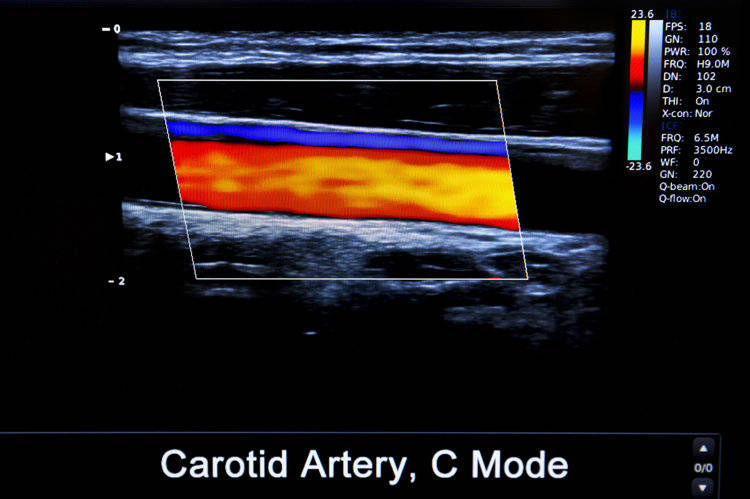

斑块是由脂肪、胆固醇、钙质、细胞残骸等物质在动脉上沉积后积累而来的,就像是沉积在水管璧上的水垢,水垢越来越多后会影响正常的水流速度。

如若颈动脉出现斑块,可能会让血液流向大脑的通道被阻塞,阻塞程度不大时身体不会有明显感觉。但后期堵塞程度越来越大,会有头晕、乏力等症状,严重的还可能诱发中风、心血管疾病。

• 斑块性质:稳定性斑块一般质地较硬,像煮熟的鸡蛋一般,不容易破也相对安全,这种斑块一般是人体老化的自然痕迹;如果是软斑块的话,则相对危险。在情绪波动、血压波动时,很容易让表皮破裂,内里的东西流出后会形成血栓,流向大脑后堵塞脑血管,诱发急性脑梗。